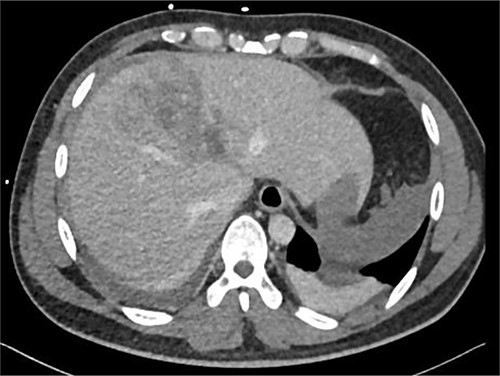

Resuscitation was carried on with 2 l of normal saline and two PRBC units to stabilize the patient. The computed tomography (CT) scan identified Grade 4 liver injury with hemoperitoneum (Fig. 2). Subsequently, the multiple bone fractures underwent surgical fixation, and post-operatively, he was hemodynamically stable. On the fifth day after admission, repeated CT scan demonstrated the liver injury with no evidence of hepatic pseudoaneurysm (Fig. 3). The patient remained stable with tolerated feeding with no abdominal pain or distension. On the Day 17, he developed abdominal pain mainly in the epigastrium, which was associated with nausea and deep epigastric tenderness. Abdominal ultrasound (US) (Fig. 4) and CT scan (Fig. 5) revealed complex, large intraparenchymal hepatic pseudoaneurysm (measuring about 58 × 41 × 30 mm) related to the left hepatic artery Segment 4 branch with surrounding hematoma located mainly at segment 4B/A ,and there was another tiny pseudoaneurysm seen at Segment 4A. Selective angiography confirmed the diagnosis of pseudoaneurysm with multiple blood supplies from Segment IV and Segment II.

Contrast-enhanced CT scan revealing a right hepatic artery pseudoaneurysm in the right lobe of the liver.